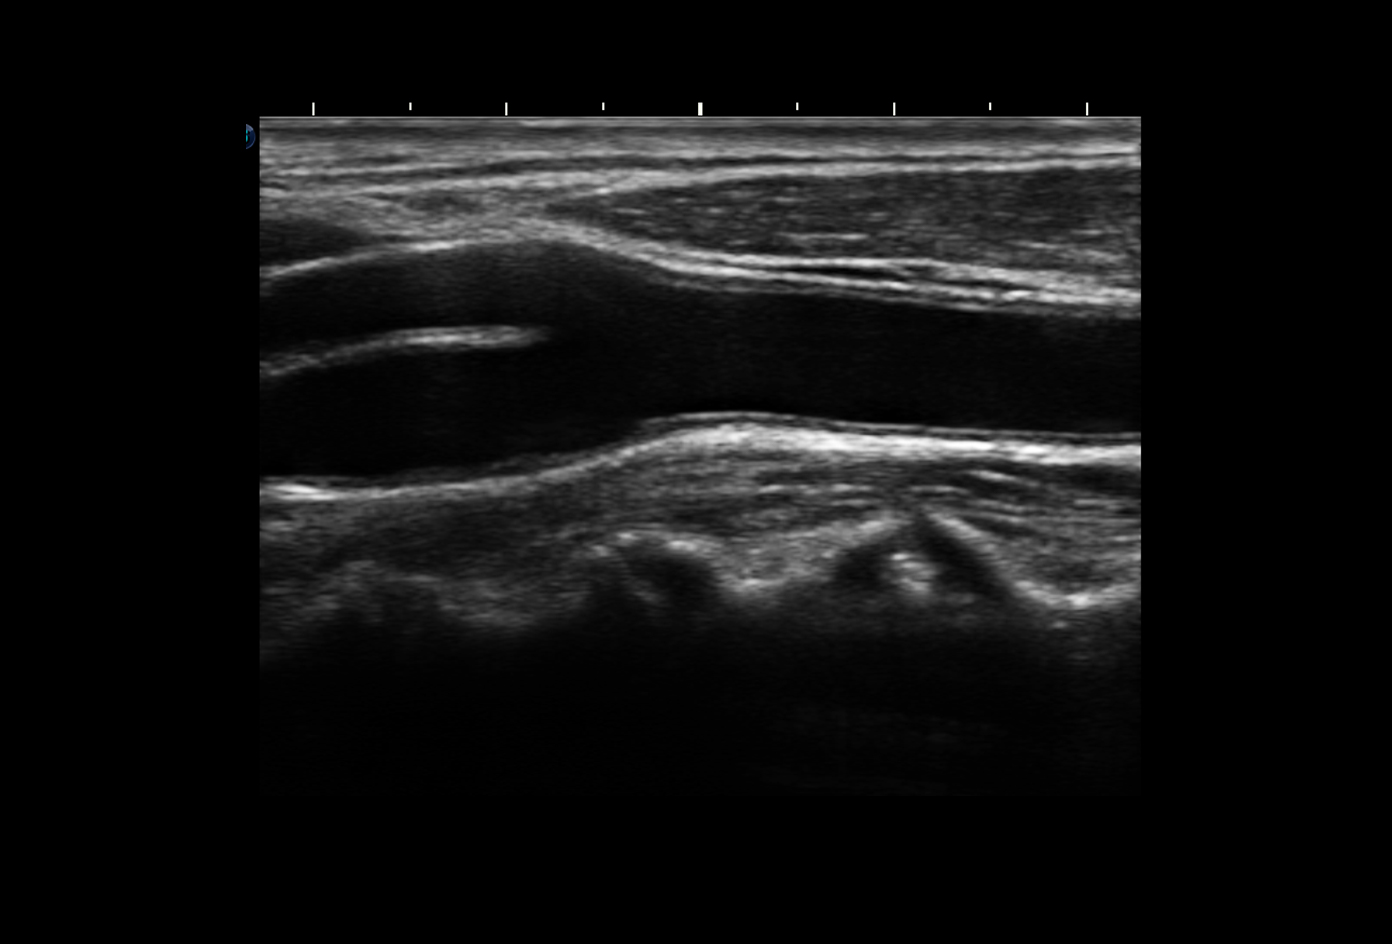

Chất lượng hình ảnh 2D trên máy siêu âm chuyên tim SonoScape P9:

Hình ảnh siêu âm Doppler thận sắc nét